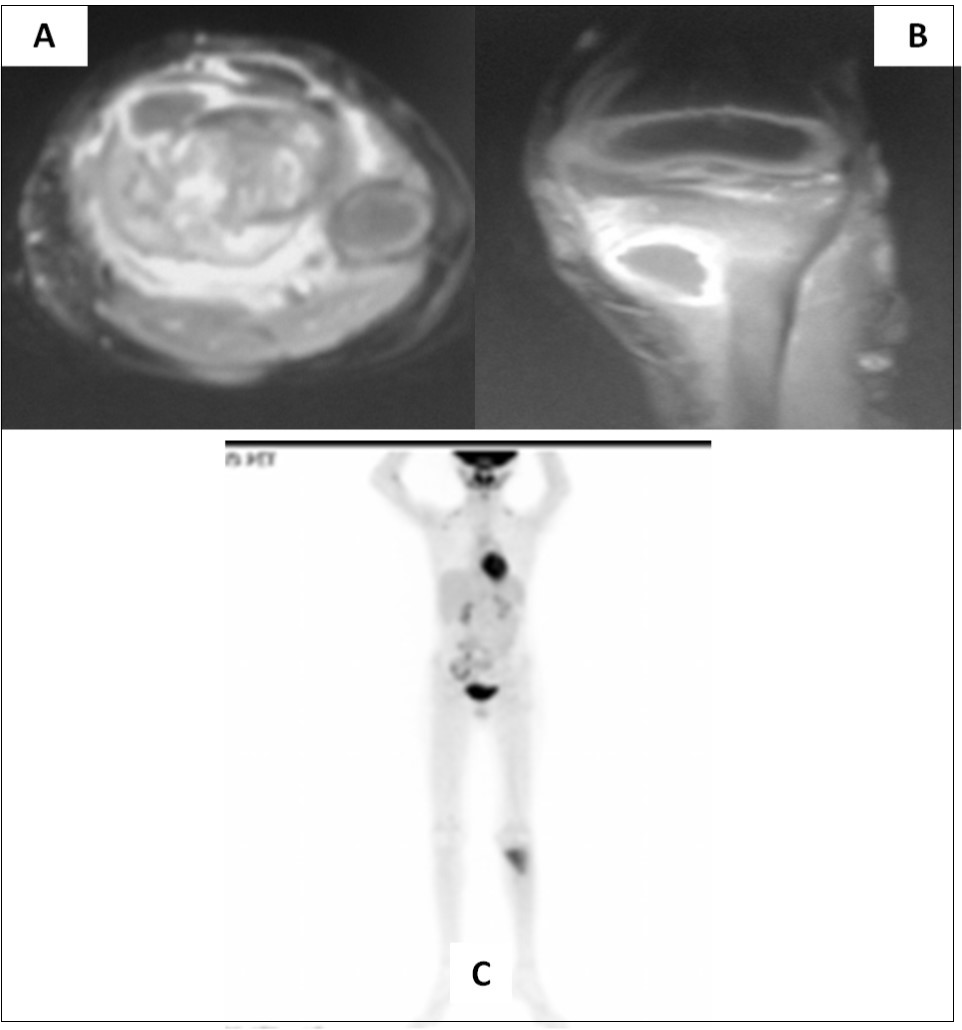

Two and half years after completion of therapy (just over 3 years from initial diagnosis), the child presented with pain in the left lower limb following a trivial injury. Local radiograph showed a large lytic/sclerotic lesion in the proximal left tibia. MRI of the left lower extremity (Figure 2A-B) confirmed the presence of this lytic/sclerotic lesion arising from the proximal tibial metaphysis with significant invasion of the adjacent soft tissues. The lesion was isointense on T1-weighted images, heterogeneously hypointense on T2-weighted images, hyperintense on STIR images with moderate post-contrast enhancement. Whole-body 18-F-fluoro-deoxy-glucose positron emission tomography/computed tomography (FDG-PET/CT) showed increased radiotracer uptake limited to the mass lesion in the proximal left tibia with a maximum standardized uptake value (SUVmax) of 6.28 suggestive of localized metabolically active tumor. There were no other areas of abnormal tracer uptake anywhere in the body ruling out disseminated disease (Figure 2C). Neuraxial imaging at this time did not reveal any local recurrence in the posterior fossa or leptomeninges confirming that the index cancer was controlled. The differential diagnosis was between second primary bone neoplasm with extensive soft tissue component versus solitary metastasis from medulloblastoma.

Figure 2.Axial (A) and coronal (B) MRI sections of left proximal tibia showing a large soft tissue component in addition to the lytic/sclerotic bony lesion. Whole body FDG-PET/CT showing increased tracer uptake localized to this lesion (C) with no significant abnormal uptake elsewhere in the body